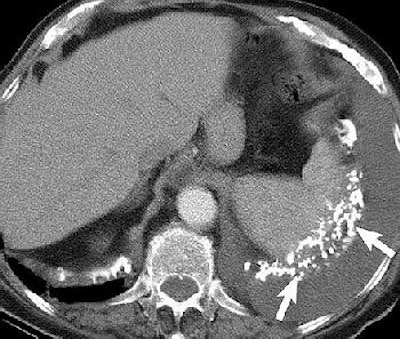

Pleural effusion in a 70-year-old man with a history of asbestos exposure and known left-sided MPM. Axial contrast-enhanced CT scans obtained at different levels show unilateral pleural effusion (P, above) with extensive calcified pleural plaques (arrows, below). Figure 1a-b, Wang ZJ, Reddy GP, et al, "Malignant Pleural Mesothelioma: Evaluation with CT, MR Imaging, and PET" (RadioGraphics 2004; 24: 105-119).